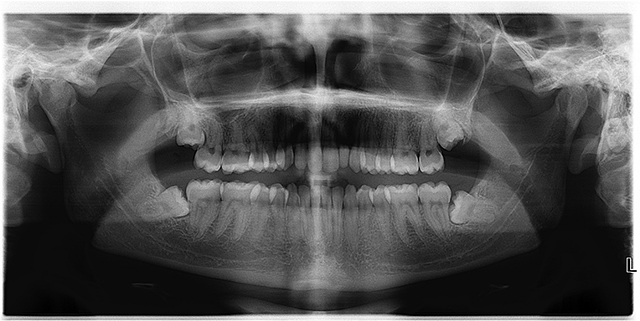

Wisdom teeth are jokingly called the dentists best friend: they almost always need to be removed or have some kind of problem with them. In this article we wish to go about explaining why wisdom tooth pain and wisdom tooth issues are so frequent, and what kind of issues they are. We also wish to describe the different kinds of problems that frequently occur with wisdom teeth, and thus can prepare you for what you may experience.

The human mouth is frequently too small to allow for the growth of wisdom teeth due to evolutional changes in the shape of the human skull. Wisdom teeth had a functional role in the mouth of homo Erectus, but as the skull changed, there is often no more room for these teeth. In these cases the wisdom teeth may grow underneath other teeth or overlapping the molars, pushing the entire row of teeth in a given direction. This is called an impacted wisdom tooth, or wisdom tooth impaction. When wisdom teeth grow in this manner, you have to remove them.

These extractions are frequently surgical tooth extractions, and an oral surgeon needs to perform it because there isn’t enough space for the dentist to perform a regular tooth extraction.

Sometimes wisdom teeth only partially erupt; only the cusps of the crown stick out, or only a portion of the tooth comes out of the gums. This is a huge problem for two reasons.

One is that the gums around it are damaged and there will be a wound around the tooth in a hard to reach the area that is difficult to clean, making it the perfect place for periodontitis to form. The second is that it will be difficult to clean, and the result is that the wisdom tooth and the gums around it will be infected.

Because of their position, all the way in the back of the mouth, wisdom teeth are more prone to tooth decay and caries. Much of the food we chew ends up being smooshed into the back of the mouth, and cleaning it is difficult, so there is more food for bacteria and more food detritus in the back where the wisdom teeth are located.

Wisdom teeth are some of the largest teeth you have; they are your third set of molars, so when they have carried, they are usually big. If you notice any changes in your wisdom teeth, contact your dentist immediately, as it is very important to nip these problems in the bud, as root canal treatments for wisdom teeth are often impossible to perform, so advanced decay usually ends with extractions.